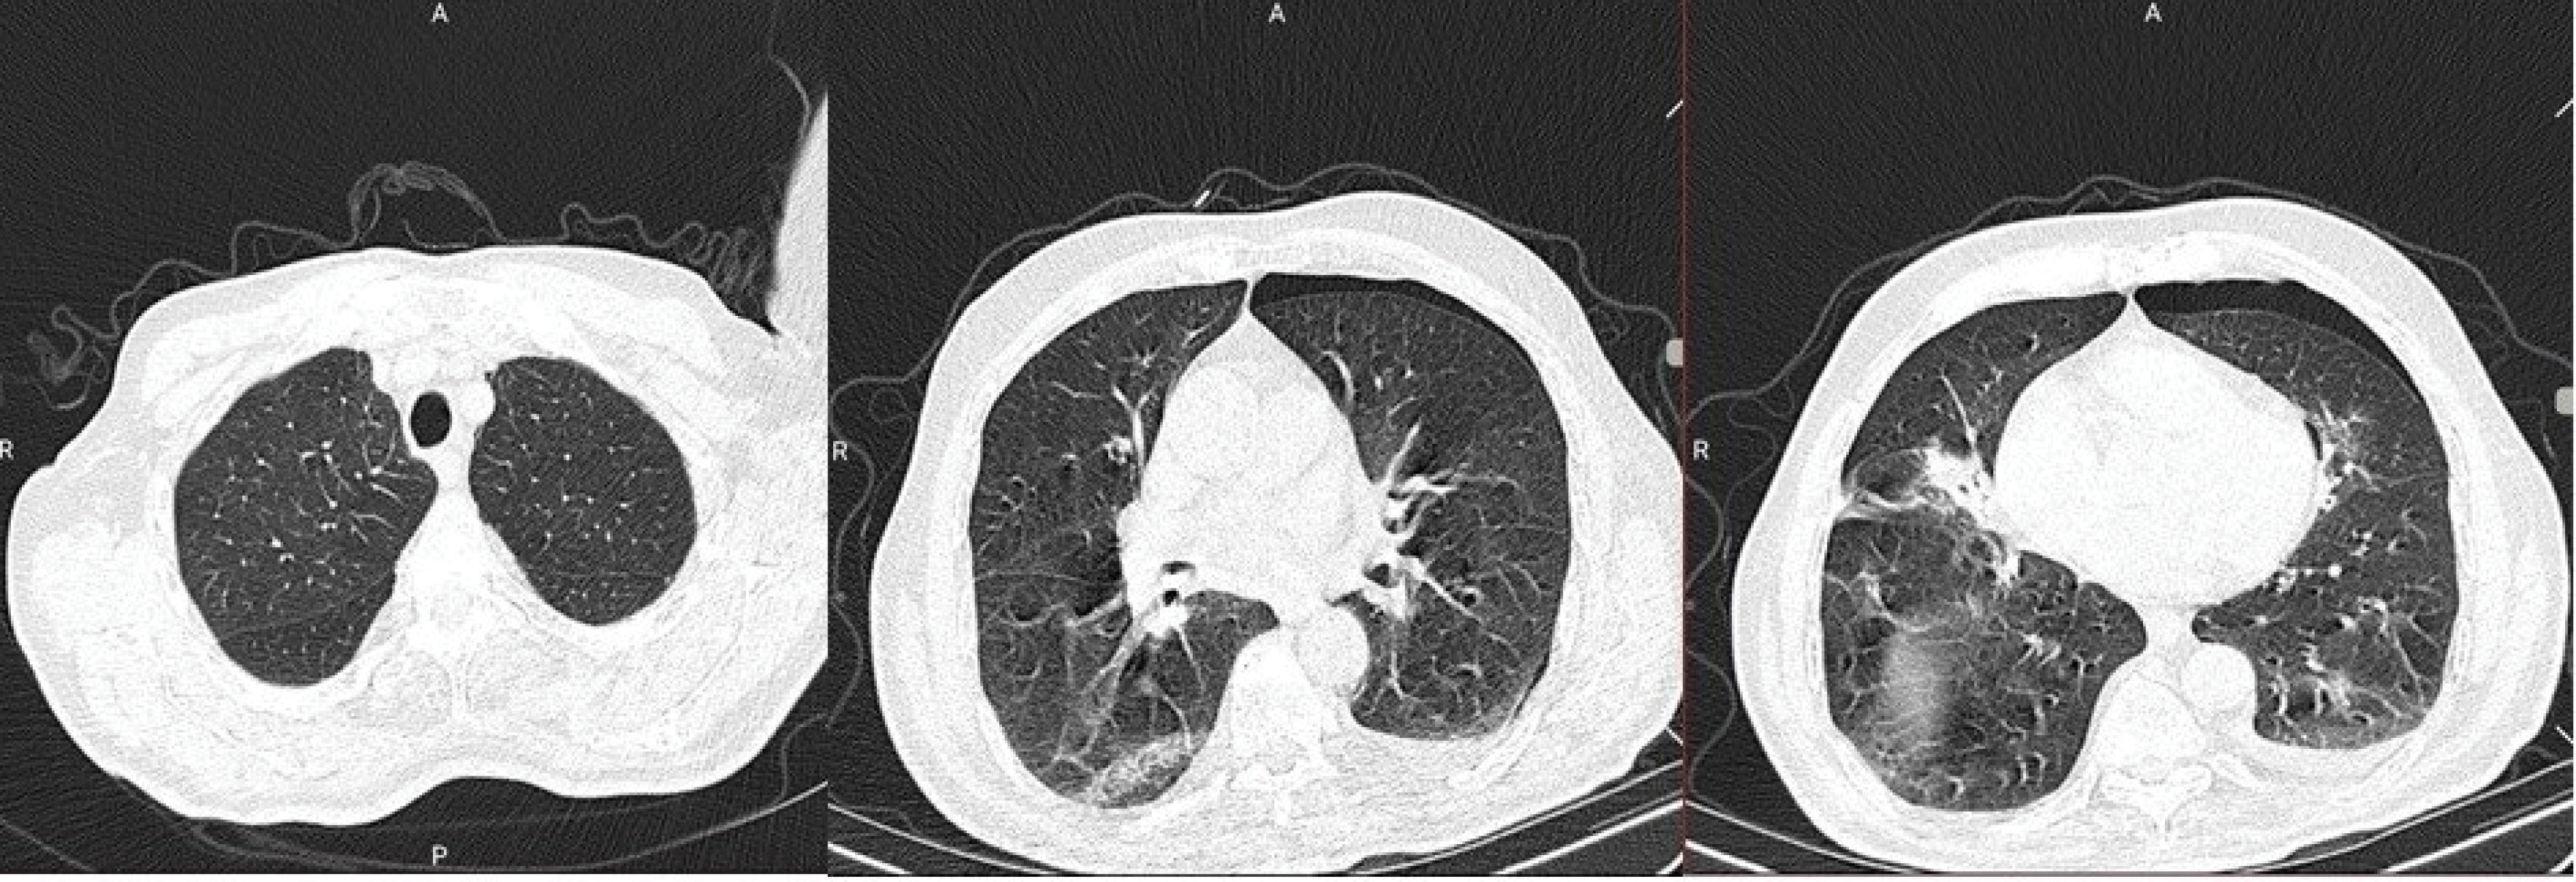

Figure 1.

First Chest CT of the patient showing posterior-peripheral ground-glass opacities, with a thin radiolucent line presenting a small pneumothorax. The patient had minimal involvement in the apex of the lungs, and involvement was mostly observed in the bases

The initial CT scan obtained on the first day of admission () showed a uni-focal peripheral ground-glass opacity in the middle segments of the right lung. A small linear line of non-existent lung texture was visible on the left lung periphery. Based on institutional guidelines, the patient was admitted, and conservative management was chosen for the pneumothorax, and the initial estimation of its size was 7% of the hemi-thoracic cavity. The results of the molecular assay obtained on the first day of admission came back positive on the third day. The patient was put on hydroxychloroquine 200 twice daily, ceftriaxone 500 mg daily and Tamiflu 75 mg twice daily. He was also given steroids (prednisolone, 40 mg, IV). The patient had a stable clinical course until the fifth day of hospitalization when the patient reported an aggregation of dyspnea and emergence of dull chest pain, localized in the periphery of the left hemithorax. The patient had an ECG took, which was normal, Troponin-I was negative, Vital signs were stable, and emergency consultation with a cardiologist did not yield any further results. Physical examination yielded no positive findings other than a mildly reduced respiration sounds on the left hemithorax.